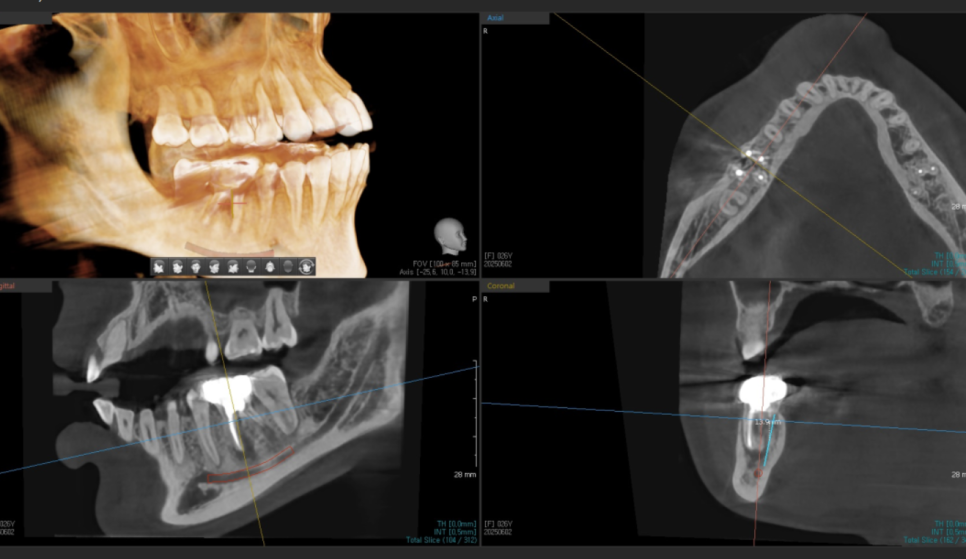

CT를 찍어보니 뼈 소실이 생각보다 많이 진행되어 있었습니다.

20602

당일 발치 후 바로 뼈이식과 함께 임플란트를 심었습니다.

이렇게 즉시 식립하면 뼈 손실을 최소화할 수 있거든요.

정확한 각도와 위치에 심어졌습니다.